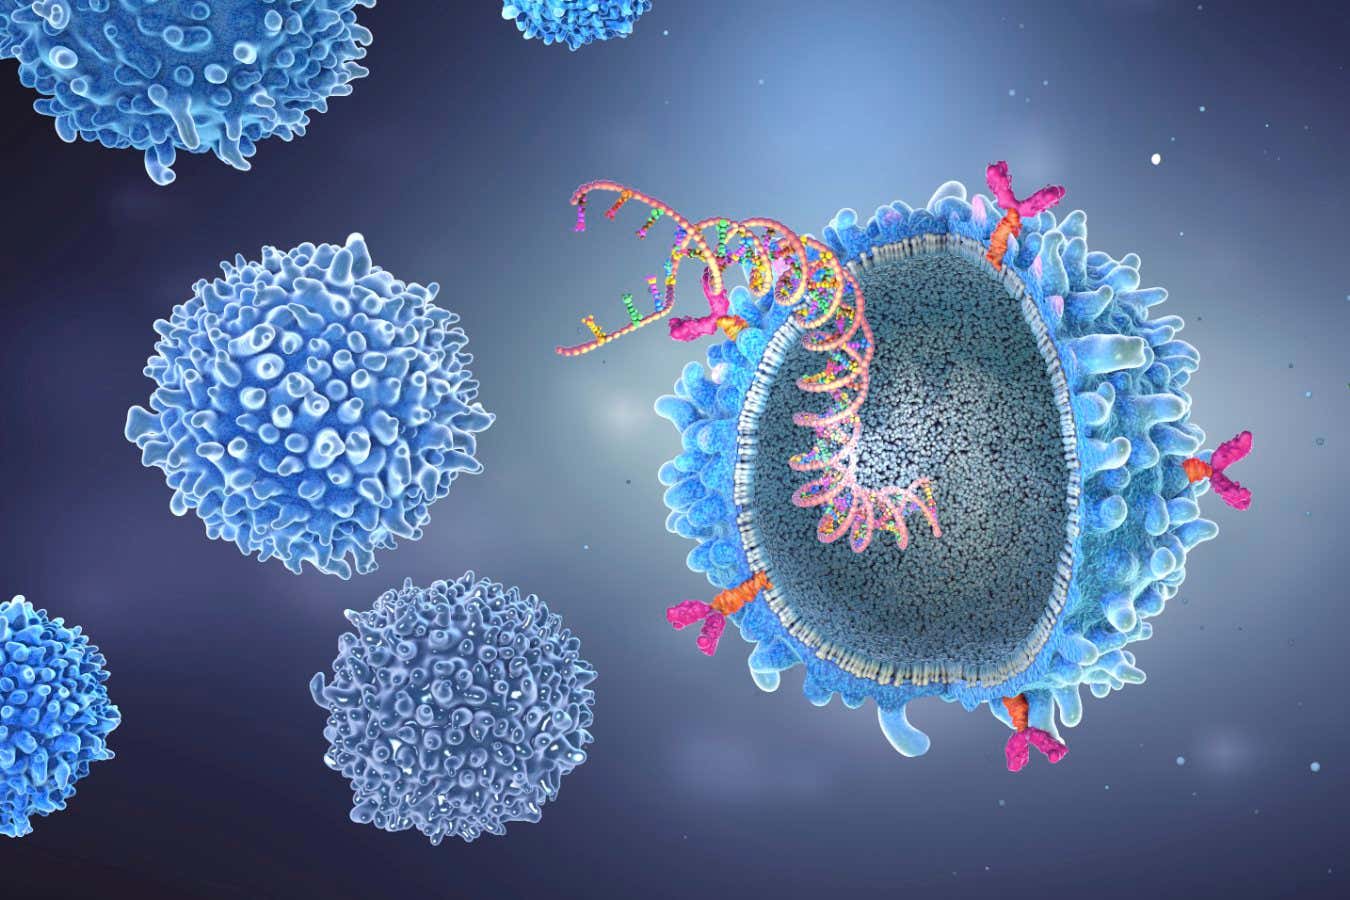

Illustration of a CAR T-cell with an implanted gene strain, resulting from the genetic modification process required for it to fight rogue cells in the bodyCHRISTOPH BURGSTEDT/SCIENCE PHOTO LIBRARY

Illustration of a CAR T-cell with an implanted gene strain, resulting from the genetic modification process required for it to fight rogue cells in the body

CAR T-cells are T-cells – immune cells that usually kill infected or cancerous cells – that are taken from the person undergoing treatment. In the lab, they are genetically engineered to make them attack a specific target and then infused back into that person.

To treat the woman, Müller’s team made CAR T-cells that target the immune cells that produce antibodies. When the modified cells were infused into her, they killed off her antibody-producing cells.